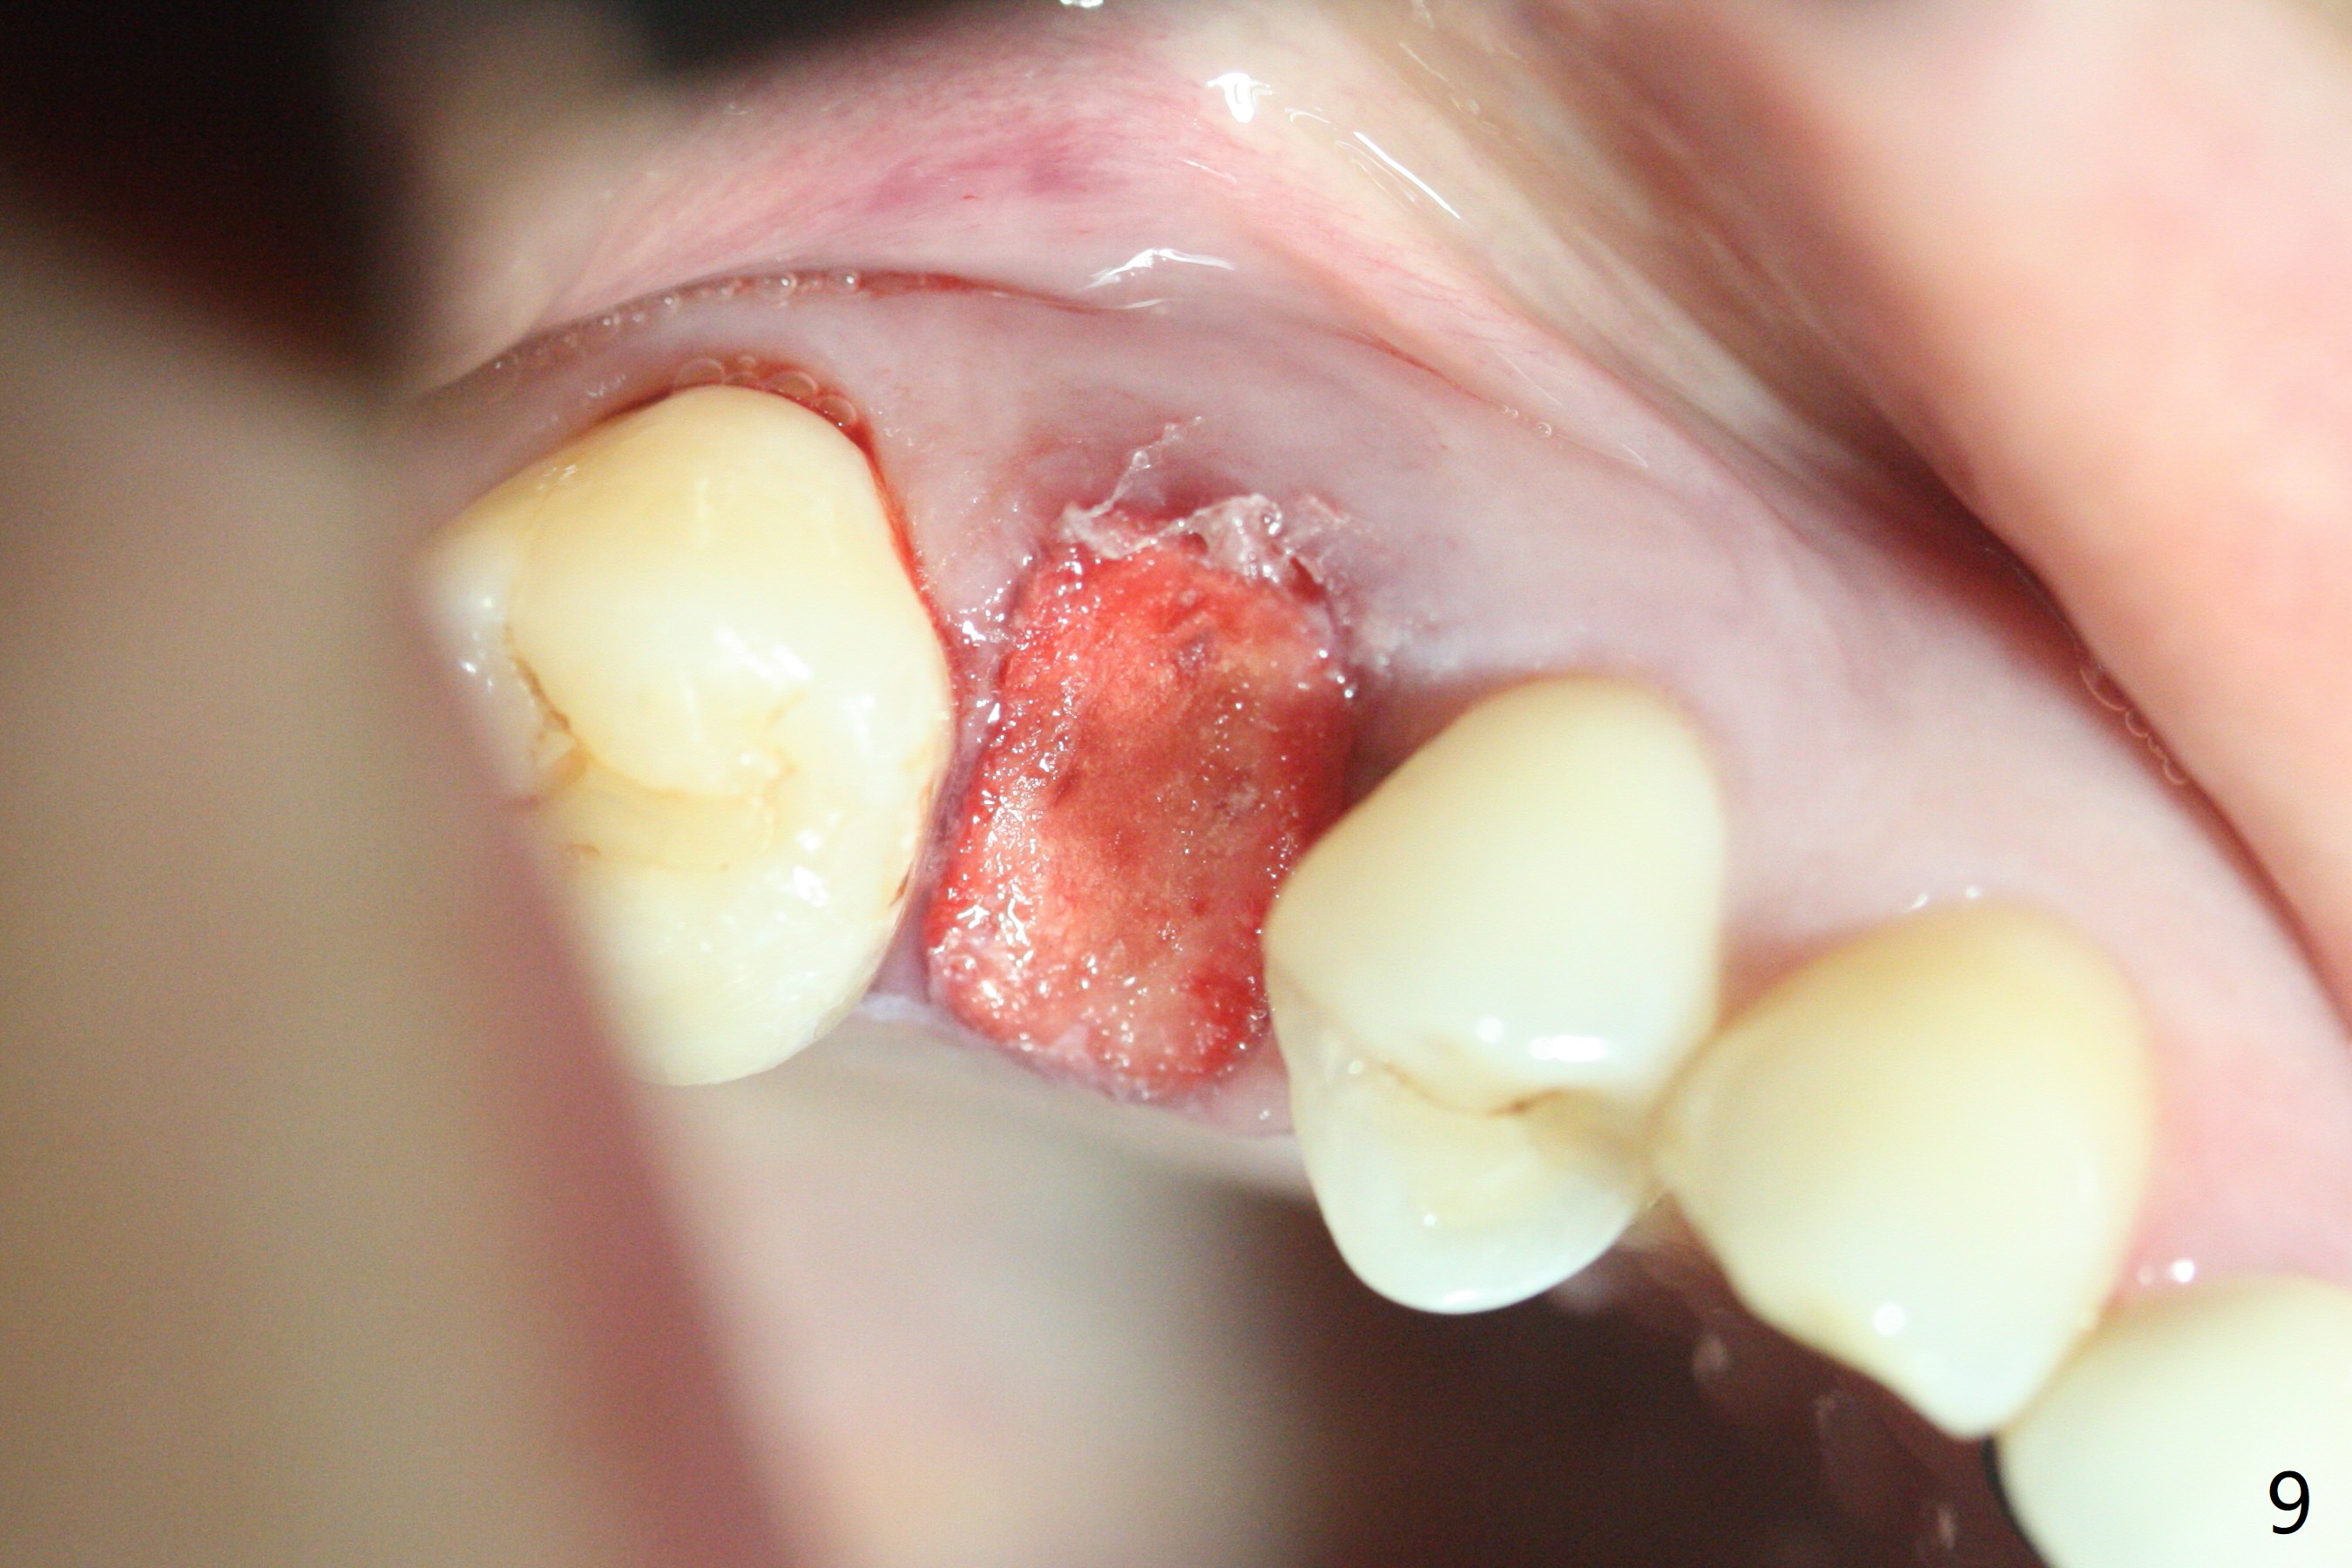

40岁女右上5近中龈下龋齿(图一),要求拔除植牙,上颌窦底板已经破坏穿孔,但是窦膜完整(图二)。清创后,放置PRF膜和粘性骨粉,用挖匙和上颌窦充填器尽量往上面推。然后放置导板,使用2.2x7.3 和3.0x7.3毫米钻头完成钻洞,可能无意中把骨粉推入上颌窦,之后利用报废植体(图三,四)完成提升,同时修补根尖缺损(利用之前放置的骨粉,图四:*,与图五(术前)对比)。当报废植体取出时,植牙窝已经形成,再放入少量骨粉,植入同样大小(之前扭力高)正式植体(不同品牌,图六,七),这时扭力低,放置愈合帽和骨粉(图七,八),以及6-9个月吸收膜,使用牙周胶水固定(图九),最后牙周敷料。术中术后几个小时没有上颌窦膜破裂迹象。术后一周牙周敷料松动,造成不适,去除时,膜好像粘附于敷料一起去除,骨粉暴露(图十),使用树脂敷料固定。后者术后一个月去除,因为局部有臭味。术后4个月切开放置愈合基台(图十一),术后五个月放置修复基台(图十二),使用塑料袖取模。术后5.5月同时放置牙冠和基台,十分顺手,口内粘固,之后同时取出,除去多余粘固剂,然后拧紧30Ncm(厂家推荐35 Ncm),一切非常顺利,觉得拍摄X光片是多余的。美中不足的是开孔(access hole)偏腭侧(图十二;由于自由手植入植体,与设计对比)。